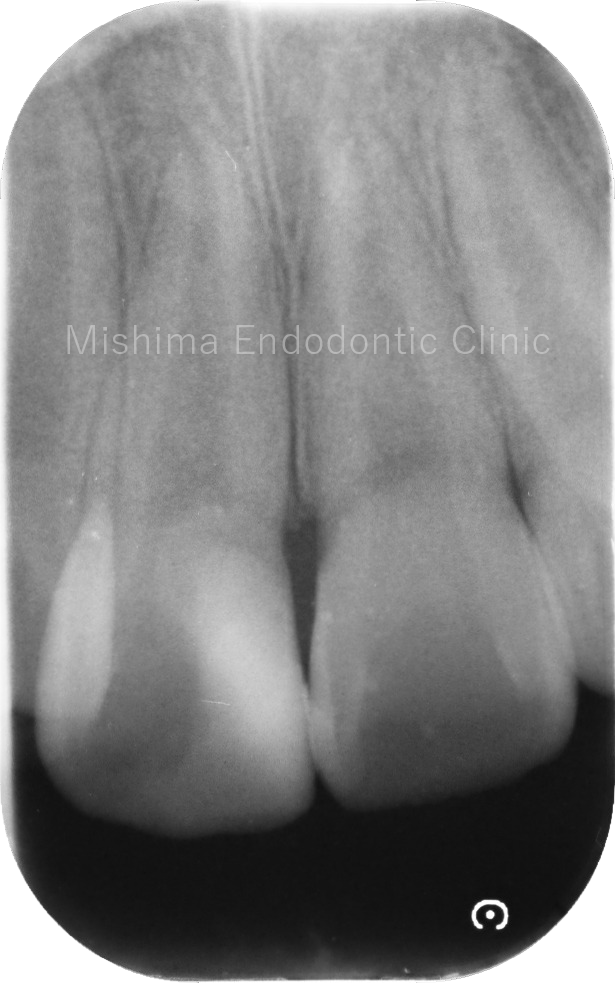

Before

術前

術直後